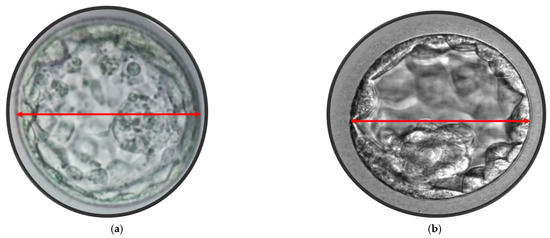

2.3. Blastocyst Morphometric Evaluation